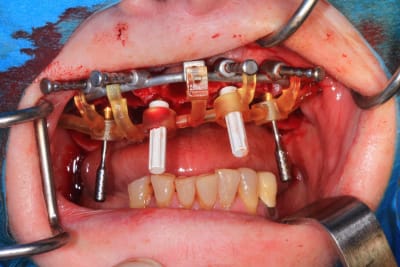

Le cas N°2 en images reelles :)

Guide métal avec support clavette, os assez fin : il est prévu un sticky bone complet : donc : lambeau avant extraction, positionnement du guide base et forage des clavettes, positionnement du guide implant, pose des piliers MU, controle des axes prothétique avec le guide pilier, collage des piliers prov sur le bridge a armature métal, occlusion nickel, sticky bone et PRF, sutures suspendues.

T’as quand même une sacrée déviation des implants / à la planification…..

Ça se voit déjà avec les implants posés à travers le guide de forage métallique qui est amha trop permissif

Et c’est confirmé par ton guide pour les piliers multiunits qui n’est même pas à fond (clavette antérieur pas mise….enfin certainement impossible à mettre)

Mais tu as raison, il y avait un peu trop de jeu au niveau du guide .

C’est le premier entièrement métallique que je fais imprimer ( Fridentech ). Il faut que je fasse un modèle avec plusieurs diamètres pour avoir le meilleur ajustage . Je pense que le mieux serait d’insérer une douille ETK. C’est ce que fait Dimitri avec ses guides métalliques codiagnostic.

Pour le guide pilier , c’était pile, mais je n’avais pas fais la photo. Je l’ai remis vite fais ( et mal ) pour la photo.

Le guide pilier est la réplique du bridge prov , en plus light pour une meilleure visibilité, donc, si je n’avais pas pu bien mettre le guide pilier, cela aurait été pire avec le bridge prov.

Mais tu peux me faire confiance.Le bridge prov était nickel, avec la clavette en place, sans que je ne doive meuler les puits préparés.